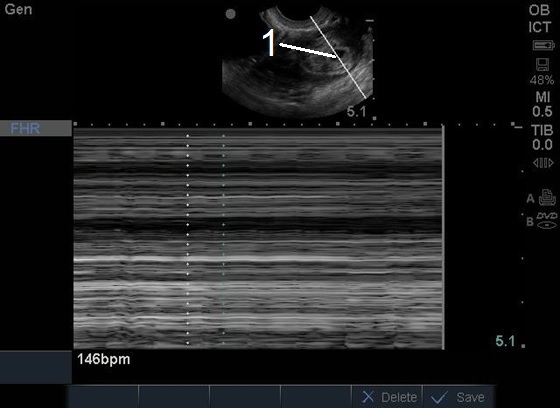

Bild 1: Transvaginaler (TV) Ultraschall des Beckens, ektopische Schwangerschaft, fetale Herzfrequenz (FHF), M-Mode